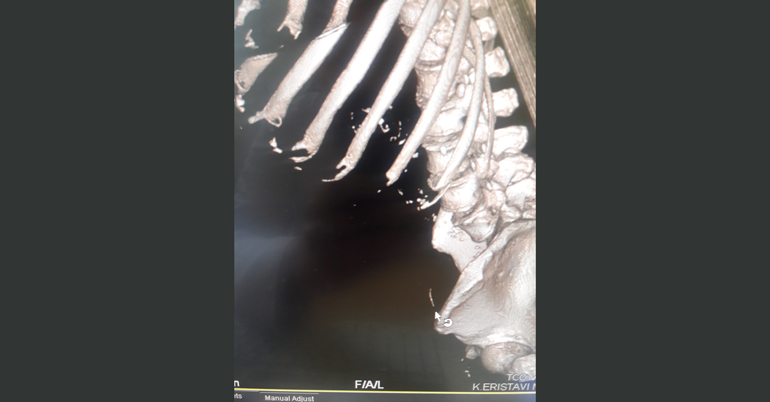

კლინიკის რადიოლოგმა ირაკლი გიგიაძემ შენიშნა, რომ წვრილი ნაწლავი უცხო სხეულით იყო დაზიანებული. დაუდგენელი სახეობის უცხო სხეული ნაწლავის სანათურიდან მუცლის ღრუში გამოდიოდა. პაციენტს ჩაუტარდა ლაპარასკოპია. მოიძებნა და ამოღებულ იქნა უცხო სხეული, ხოლო წვრილი ნაწლავის დაზიანებული უბანი გაიკერა.

უცხო სხეული, რომელიც ქირურგებმა პაციენტის წვრილი ნაწლავიდან ამოიღეს, აღმოჩნდა მეტალის მავთული (ჭურჭლის სახეხის შემადგენელი ნაწილი), რომლის ზომაც 4 სმ–ს შეადგენდა და კუჭ–ნაწლავში საკვებიდან მოხვდა.